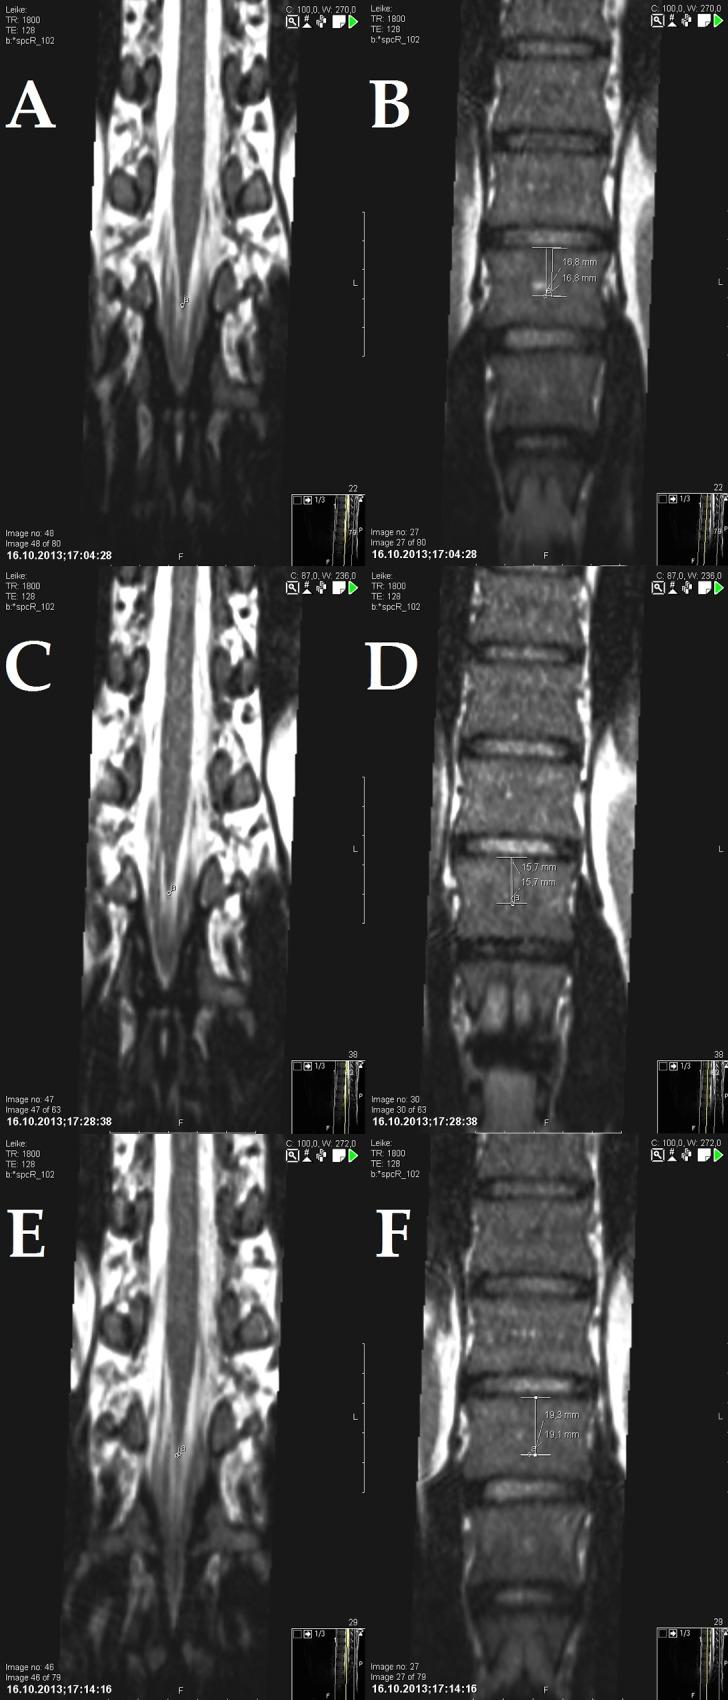

Ten asymptomatic volunteers were scanned with a 1.5T magnetic resonance (MR) scanner using T2 weighted spc 3D scanning sequences and a device that permits greater ranges of SLR. Displacement of the conus medullaris during the unilateral and sham SLR was quantified reliably with a randomized procedure. Conus displacement in response to unilateral and sham SLRs was quantified and the results compared.

The conus displaced caudally in the spinal canal by 3.54±0.87 mm (mean±SD) with unilateral (p≤.001) and proximally by 0.32±1.6 mm with sham SLR (p≤.542). Pearson correlations were higher than 0.99 for both intra- and inter-observer reliability and the observed power was 1 for unilateral SLRs and 0.054 and 0.149 for left and right sham SLR respectively.